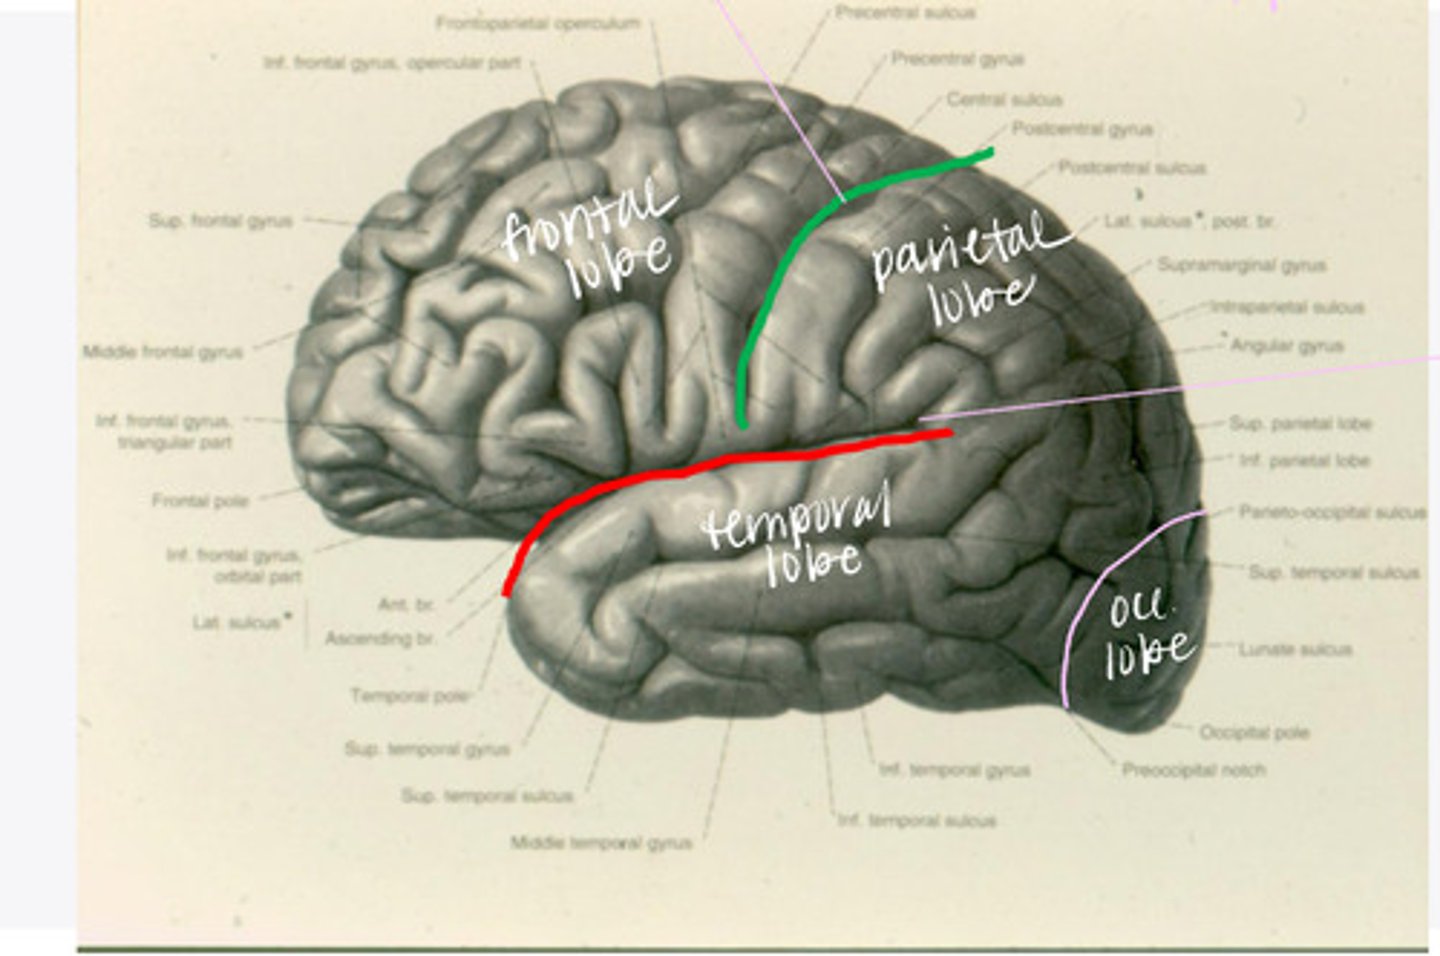

-frontal

-parietal

-temporal

-occipital

What are the 4 lobes of the brain?

central sulcus

What sulcus differentiates the frontal from the parietal lobe?

lateral sulcus

What sulcus differentiates the frontal from the temporal lobe?

-precentral gyrus

-superior frontal gyrus

-middle frontal gyrus

-inferior frontal gyrus

The frontal lobe is divided into what 4 gyri?

-opercular

-triangular

-orbital gyrus

What are the 3 divisions of the inferior frontal gyrus?

-post-central gyrus

-superior parietal lobule

-inferior parietal lobule

What are the divisions of the parietal lobe?

-supramarginal gyrus

-angular gyrus

What are the divisions of the inferior parietal lobule?

-superior temporal

-inferior temporal

What are the 2 major sulci of the temporal lobe (on lateral view)?

-superior temporal

-middle temporal

-inferior temporal

What are the 3 major gyri of the temporal lobe (on lateral view)?

everything posterior to the line connecting the parietooccipital sulcus and the preoccipital notch

Where is the occipital lobe located in a lateral view of the brain?